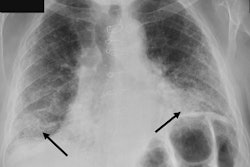

A representative set of chest x-rays of male patients, with the numbers on the top of each image representing the actual and computed heights (in parentheses). Image courtesy of Clinical Nutrition Open Science through CC BY 4.0.The team based its statistical analysis on the comparison of the model's predictions against the original height and weight values using Pearson's correlation coefficients.

According to the findings, the correlations between the model's predicted values and actual values for males and females were 0.855 and 0.81, while the correlation coefficients for weight for males and females were 0.793 and 0.86.